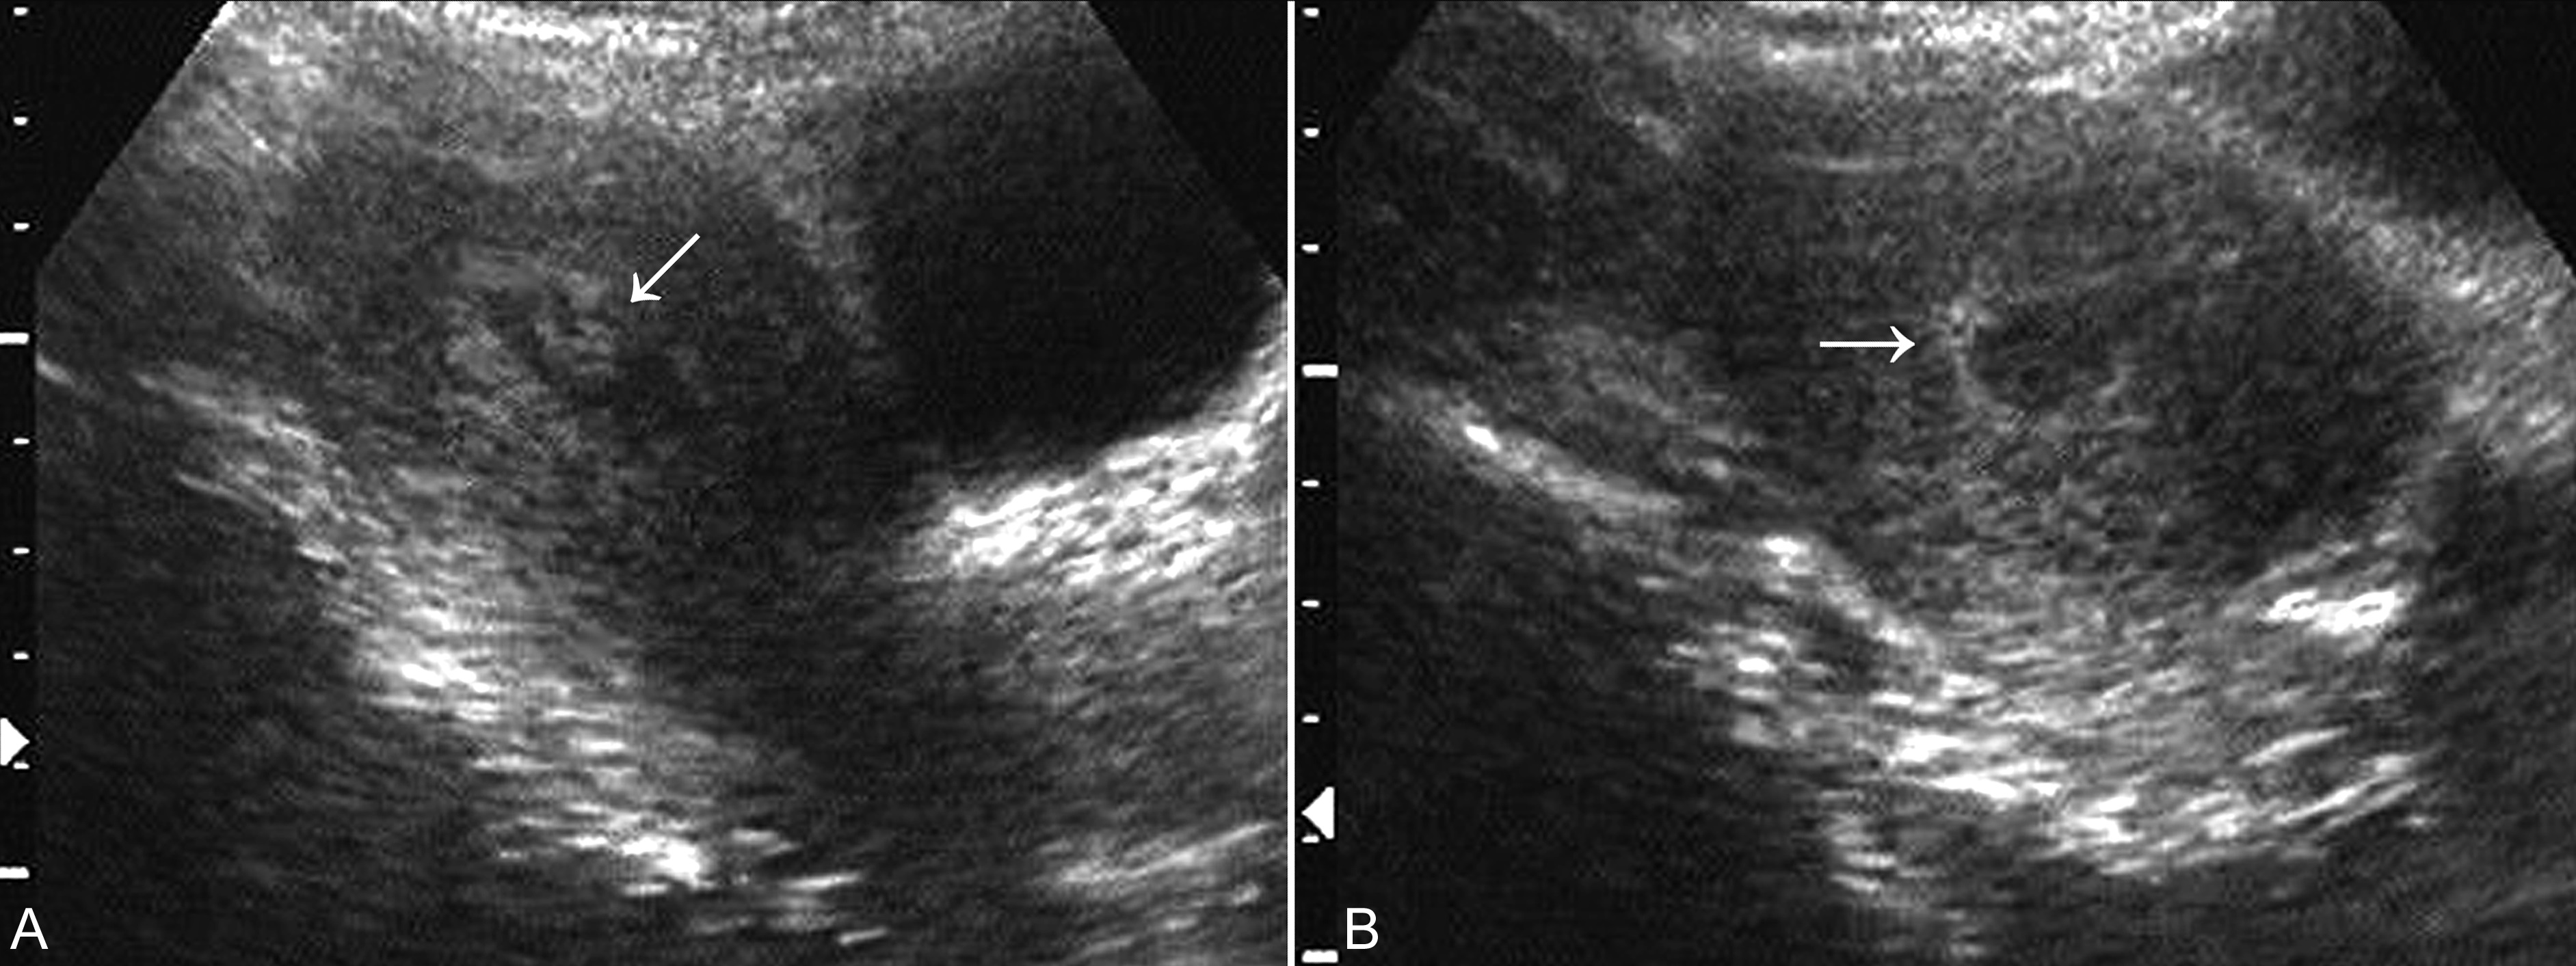

子宫小于停经月份,羊水部分吸收或完全消失,妊娠囊缩小或并其内部结构消失,宫腔内可见不规则妊娠产物形成的不均匀回声(图6),较晚的过期流产可显示胎儿骨骼形成的不规则强回声。结合临床可以诊断为过期流产。

图6 不全流产声象图:箭头示宫腔内不均匀回声,清宫证实为胚胎产物

(六)孕卵枯萎

子宫及其内部的妊娠囊小于停经月份,发生早期子宫大小可能无明显变化,孕囊大小、位置和形态可以显示正常,但子宫蜕膜反应多较轻;病程较长时可以发现孕囊变形或皱缩,内部无胚胎回声。一般认为,经阴道超声检查妊娠囊平均内径25mm无胚胎显示、或显示妊娠囊两周后复查不能显示胚胎回声、或可显示胚胎回声,但无心脏活动时均提示孕卵枯萎、胚胎早期死亡(图7)。正常发育的胚胎心脏活动几乎与胚胎同时显示,当胚胎>5mm时仍无原始心脏的搏动,即可认为孕卵枯萎、胚胎早期死亡。

图7 孕卵枯萎声象图:孕囊内未见胚胎显示